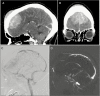

The archetypal imaging characteristics of meningiomas are among the most stereotypic of all central nervous system (CNS) tumors. In the era of plain film and ventriculography, imaging was only performed if a mass was suspected, and their results were more suggestive than definitive. Following more than a century of technological development, we can now rely on imaging to non-invasively diagnose meningioma with great confidence and precisely delineate the locations of these tumors relative to their surrounding structures to inform treatment planning. Asymptomatic meningiomas may be identified and their growth monitored over time; moreover, imaging routinely serves as an essential tool to survey tumor burden at various stages during the course of treatment, thereby providing guidance on their effectiveness or the need for further intervention. Modern radiological techniques are expanding the power of imaging from tumor detection and monitoring to include extraction of biologic information from advanced analysis of radiological parameters. These contemporary approaches have led to promising attempts to predict tumor grade and, in turn, contribute prognostic data. In this supplement article, we review important current and future aspects of imaging in the diagnosis and management of meningioma, including conventional and advanced imaging techniques using CT, MRI, and nuclear medicine.